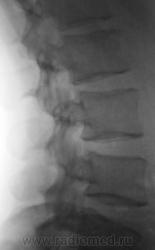

Пациент с болями в пояснице, направлен на рентгенологическое исследование поясничного отдела позвоночника.

задний спондилолистез L3,L4. сакрализация L5.признаки остеохондроза.аномалия тропизма L3-L4 справа ,L5 с обеих сторон.

При всем уважении к коллеге stovbav, лестничный микроретролистез L-2-L-3-L-4 может инициировать такие боли в спмне, что "мама, не горюй". А удлинение задне-нижних углов тел L-3,L -4 запросто могут оказаться косвенными признаками дорсальных протрузий диска..

Самый начальный деформирующий спондилоз. Листеза нет. Справа несколько небольших теней, могущих быть кокрементами в мочевых путях...